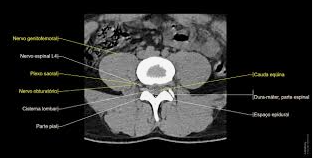

Arquitetura Moderna

Coluna Lombar

Corte Lombar.